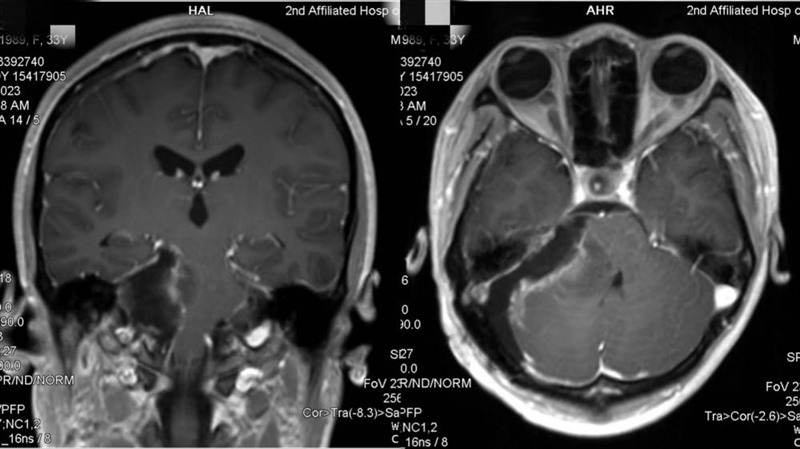

到医院一查,右侧桥小脑角区有占位性病变,在接诊医生的建议下,力力被转入该院神经外科,找到了该科主任谢宗义教授。经进一步检查,患者颅内病变直径达5.2cm,被确诊为:罕见巨大听神经瘤。

▲术前核磁共振成像(MRI)/图源 重医附二院

虽然手术抽丝剥茧般地进行了近10小时,所幸结果非常令人满意。术后患者未出现明显神经功能损伤,脑干功能正常,面部神经功能也得到了良好的保护。“感谢你们,让我回归正常生活了!”出院前,力力向谢宗义教授团队表达感谢。